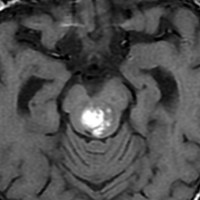

海綿状血管腫はMRIの撮影条件によっていろいろな見え方をします

腫瘍から少し出血したために,患者さんはけいれん(てんかん発作)を起こしました。左のT1強調画像では出血を疑います。中央のT2強調画像では海綿状血管腫の周りに脳浮腫があるために白くぼやけた部分があります。右の造影剤を使ったMRIでは造影剤が入るところがほどんど無いことがわかります。側頭葉の海綿状血管腫は側頭葉てんかんという症状で発症することが多いです。